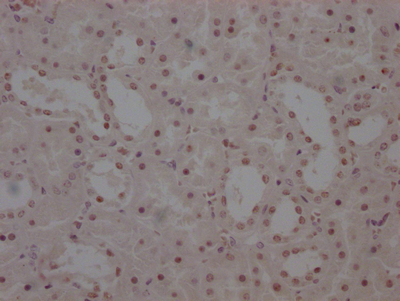

The image on the left is immunohistochemistry of paraffin-embedded Human ovarian cancer tissue using CSB-PA969280(IRS2 Antibody) at dilution 1/100, on the right is treated with synthetic peptide. (Original magnification: ×200)

The image on the left is immunohistochemistry of paraffin-embedded Human breast cancer tissue using CSB-PA969280(IRS2 Antibody) at dilution 1/100, on the right is treated with synthetic peptide. (Original magnification: ×200)